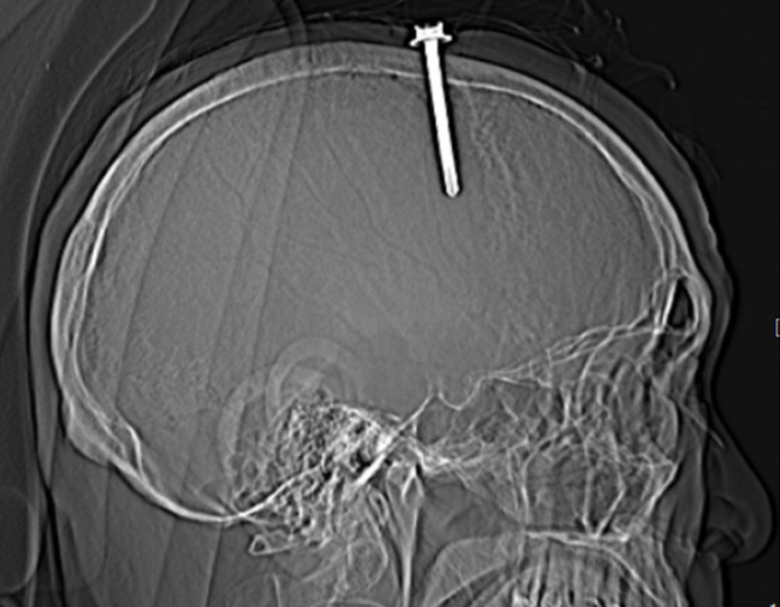

Hình ảnh chiếc đinh sắt đâm xuyên sọ não khi chụp cắt lớp vi tính.

Thạc sĩ, bác sĩ Nguyễn Hữu Quý – Bác sĩ khoa Phẫu thuật Thần kinh – Lồng ngực, Trưởng kíp phẫu thuật cho biết, qua thăm khám lâm sàng và kết quả chụp cắt lớp vi tính sọ não cho thấy bệnh nhân có vết thương xoang tĩnh mạch dọc trên do dị vật kim loại cắm vào vùng đỉnh bên trái, cạnh xoang tĩnh mạch dọc trên. Dị vật có đường kính 0.5cm, chiều dài 5,1cm. Các bác sĩ đã khoan sọ xung quanh đinh, mở volet xương sọ lấy đinh ra ngoài.